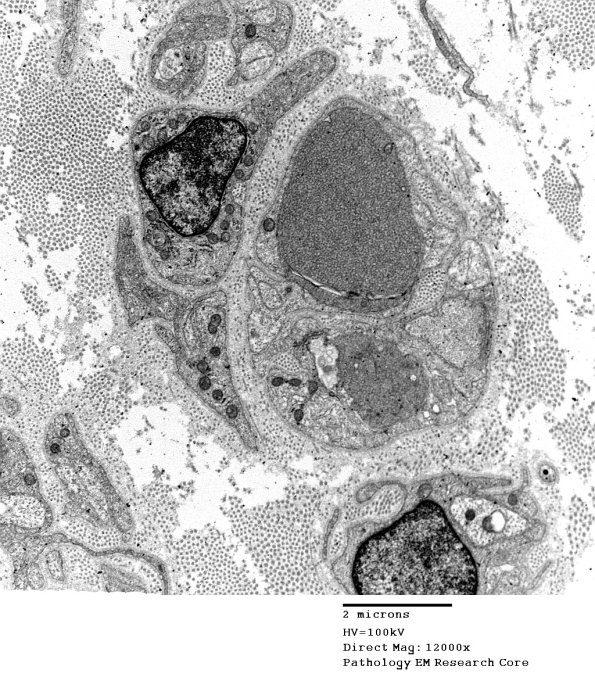

1B1A,B There are two dystrophic axons in this case which contain classical anastomosing tubulovesicular elements and a cleft (arrow, 1B2) which represent the most common appearance in this biopsy. (electron micrographs)